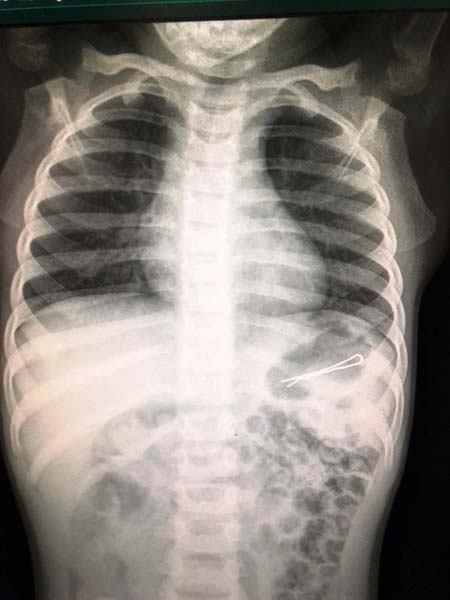

د. هنو من مشفى صفد ينقذ حياة طفل بلع مشبك شعر - صور

علم مراسل موقع بانيت وصحيفة بانوراما من مصادر طبيّة في مستشفى زيف في صفد أن الطواقم الطبية نجحت هذا الأسبوع بإنقاذ حياة طفل ( 3 سنوات ) بعد أن أُحضر الى

تصوير مكتب الناطق بلسان مستشفى زيف في صفد

المستشفى وفي بطنه مشبك شعر بطول 6 سنتمترات .

وعانى الطفل من صعوبة في التنفس ، مما شكل خطرا على حياته الى أن قام الطبيب بيان هنو، الطبيب المختص في طب الأطفال الباطني باجراء عملية للطفل ونجح بإخراج المشبك دون أن يتسبّب بأي ضرر جانبي .

هذا وشعر الطفل بتحسّن كبير بعد انتهاء العملية وتم تسريحه الى البيت .